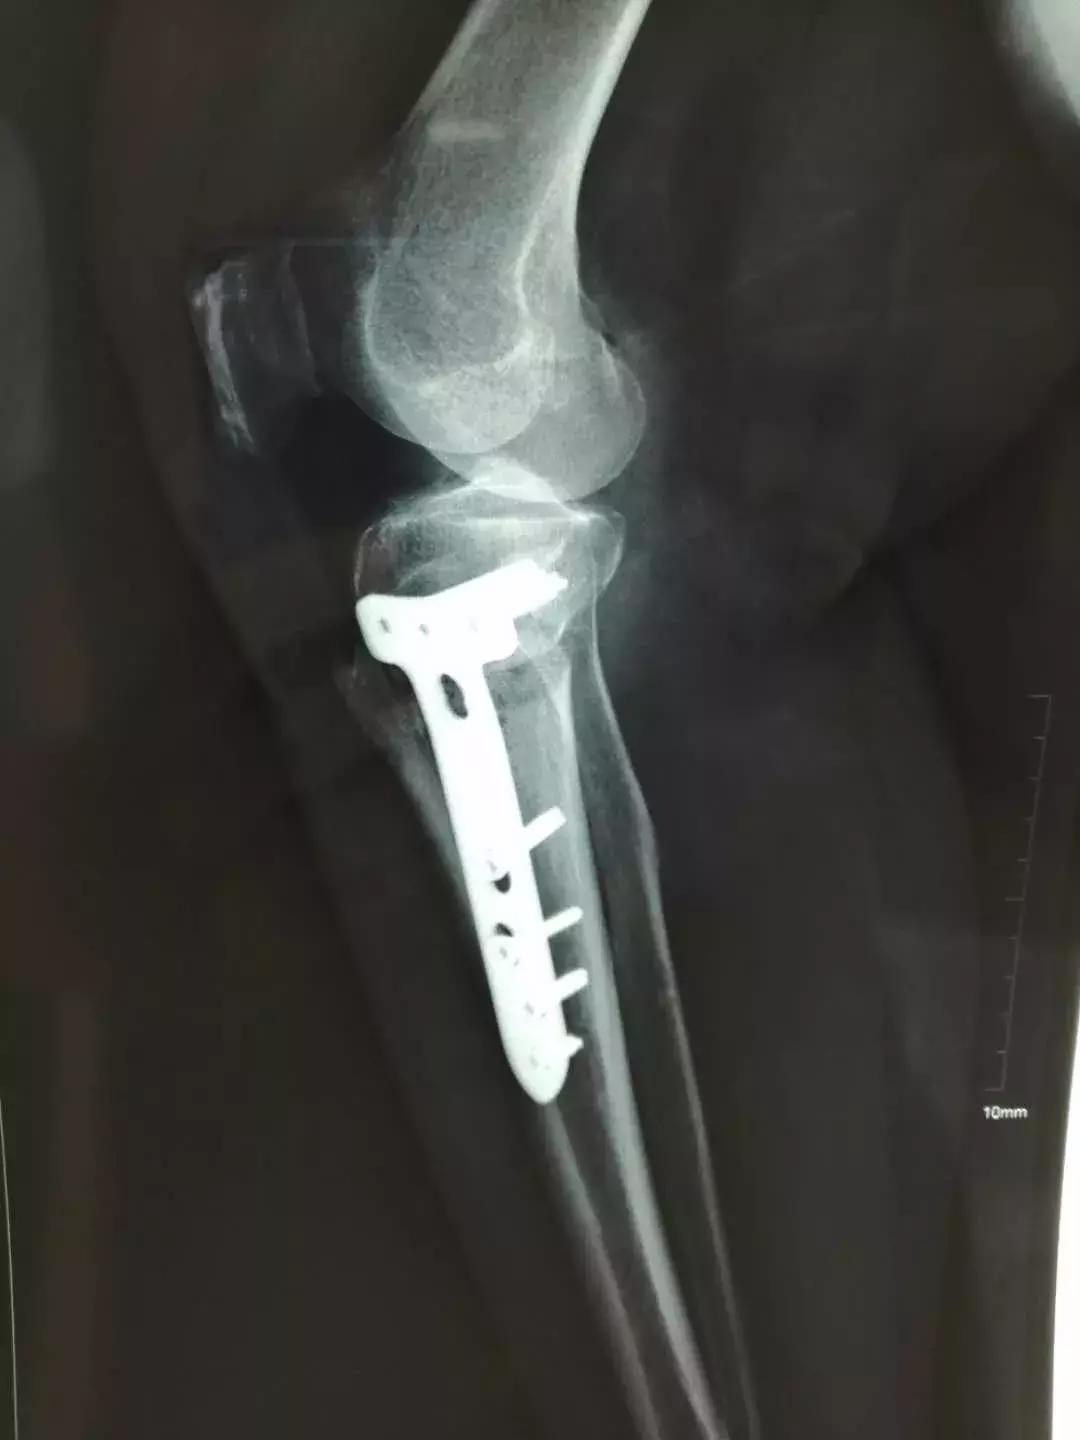

患者入院后,骨科医护人员根据患者身体症状,完善相关检查,在张云海博士的指导下,邱生海主任及闫煜军主管医师制定了精确而详细的手术方案及术后康复方案。25日,张云海博士为患者实施了HTO手术,骨科医护人员全程配合,手术用时2小时50分,进行顺利。矫正了患者膝关节内翻畸形,恢复了关节的正常力线及功能,缓解了疼痛症状。

术后第二天,患者下肢力线及膝关节功能均得到恢复,行走时膝关节疼痛症状症状明显缓解,逐步恢复正常生活。在保留自己的关节同时避免了关节置换,患者及家属非常满意。